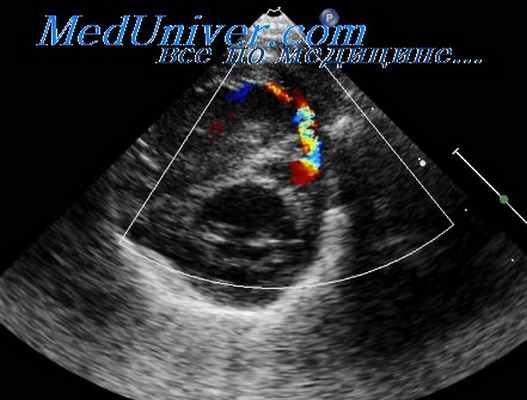

ЭхоКГ (В-режим и В-режим с ЦДК) вторичного ДМПП.

С помощью эхокардиографического исследования возможно визуализировать дефект межпредсердной перегородки, уточнить его характер (первичный или вторичный), оценить направление сброса через дефект (рис. 6, 7).